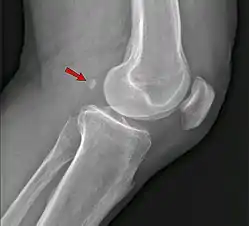

Ankle

Accessory bones of the ankle.[13]

Accessory bones at the ankle mainly include:

• Os subtibiale, with a prevalence of approximately 1%.[14] It is a secondary ossification center of the distal tibia that appears during the first year of life, and which in most people fuses with the shaft at approximately 15 years in females and approximately 17 years in males.[14]

• Os subfibulare, with a prevalence of approximately 0.2%.[15]

Os trigonum (further described below) may also be seen on an ankle X-ray.